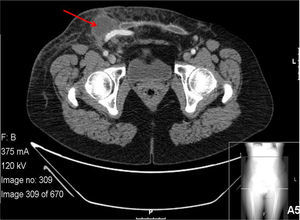

Pus was collected and gram stain and cultures were positive for methicillin sensitive Staphylococcus aureus (MSSA). The patient was submitted to conservative treatment with local surgical abscess drainage, “in situ” application of VAC-therapy and double bactericide and bacteriostatic antibiotic regimen with intravenous daptomycin and rifampicin for 3 weeks with good evolution and total remission of fever, local or systemic signs of infection (Fig. 2). The patient was maintained with oral trimetoprim-sulfametoxazol bid, for more 6 months.